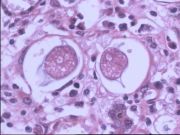

| 2021年12月10日 (五) 13:17 | 16号切片-鳞癌(角化珠)-镜下观2.jpg (文件) |  |

66 KB | Cirno.9 | 基于MsUpload的文件上传 | 1 |

| 2021年12月10日 (五) 13:17 | 16号切片-鳞癌(角化珠)-镜下观1.jpg (文件) |  |

80 KB | Cirno.9 | 基于MsUpload的文件上传 | 1 |